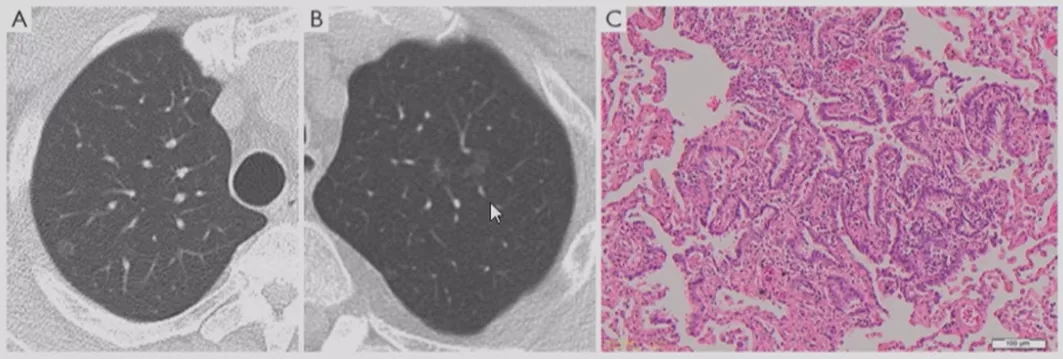

不典型腺瘤样增生(AAH)

在临床上经常手术切除后发现是AAH,关于AAH的病人是否需要手术还存在很大的争议,有的认为不需要手术,观察就可以。那么我们在术前怎么评判是否为AAH?其实具有一定特征。一般来说,多位于肺外周,多<5mm,圆形或类圆形,边界清楚,多发更常见,绝大部分是均匀的纯磨玻璃影,里边没有实性成分。组织学检查AAH呈轻度到中度非典型立方柱状上皮细胞沿肺泡和呼吸性细支气管上皮增殖,无浸润,这样在临床上诊断AAH应该没有问题。但是,如下图所示,这个病人是多灶性病变,现在多灶性结节有所增多,会给临床的处理上带来一定压力。

原位癌(AIS)

接下来再发展就是原位癌。一般来说,多位于肺外周,多为单发,病灶比AAH更大,形状可为圆形、类圆形或不规则,边界清楚,可为纯磨玻璃影。现在计算机可以测量CT值,我们应该定量分析,观察CT值,不透明程度较AAH高。组织学呈纯粹的贴壁生长,无基质、血管或胸膜浸润。一旦遇到密度稍微高一点的磨玻璃结节,要谨慎,它很可能已经是原位癌,此时手术仍然是非常理想的效果。